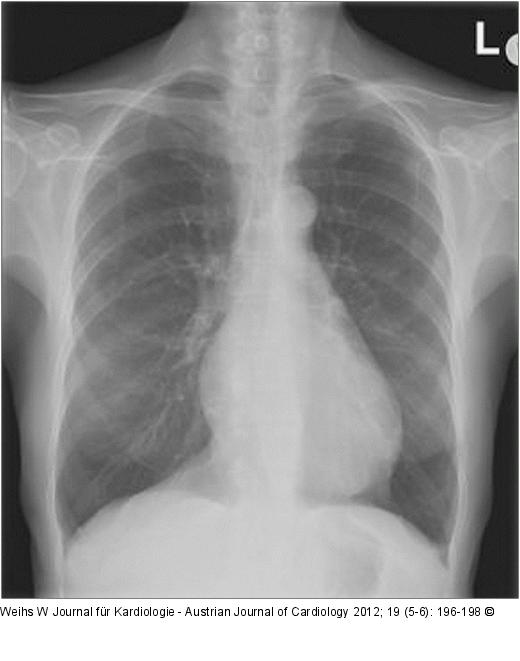

Abbildung 2: Thorax-Röntgen Thorax-Röntgen: linksventrikulär betontes Herz, keine Stauungszeichen, Aortensklerose, keine Infiltrate, dorsal adhärenter Recessus, suspekte Zeichen einer Rechtsherzbelastung. |

Thorax-Röntgen: linksventrikulär betontes Herz, keine Stauungszeichen, Aortensklerose, keine Infiltrate, dorsal adhärenter Recessus, suspekte Zeichen einer Rechtsherzbelastung. |